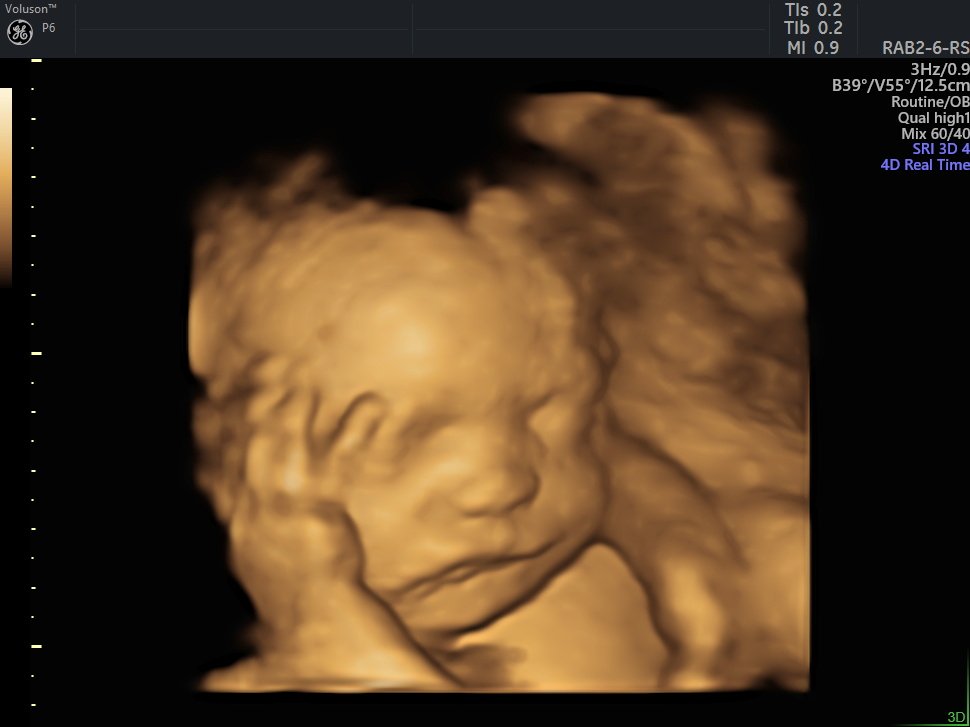

4 Boyutlu (Renkli) Ultrason ve Doppler Ultrasonografi

4 D Ultrasonografi